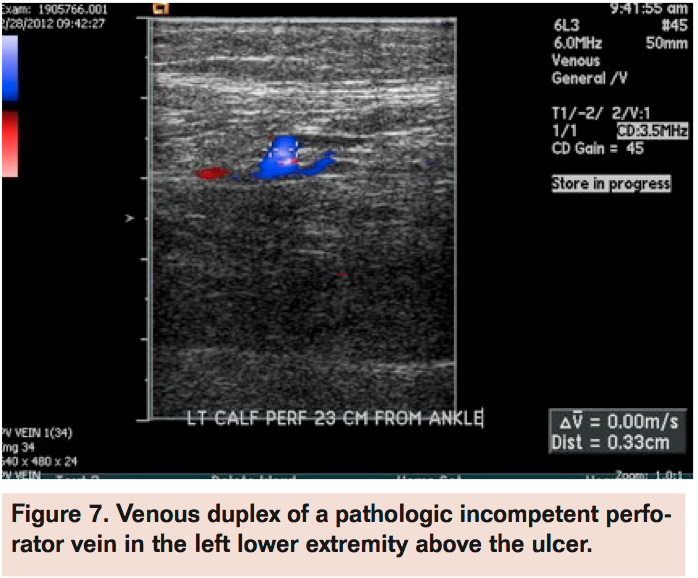

Angiogram of the left common femoral artery with runoff revealed distal left superficial femoral artery occlusion (Figure 1A) with reconstitution of the distal popliteal artery and 2-vessel runoff into the left foot via the anterior tibial and peroneal arteries (Figure 1B). Revascularization of the occlusion was performed using balloon angioplasty and stent placement (Figure 2A) with good angiographic result and runoff (Figure 2B). She had complete resolution of her claudication symptoms, but returned 1 year later with ulceration of the medial aspect of her left foot above the medial malleolus. Repeat angiogram revealed restenosis of the stent (Figure 3A) and re-occlusive disease of the distal popliteal artery stent extending into the anterior tibial artery (Figure 3B) requiring atherectomy and balloon angioplasty for successful revascularization (Figure 4). However, her ulceration progressed despite revascularization, prompting further evaluation of the etiology of her ulcer (Figure 5). A venous Doppler study of the left lower extremity revealed severe reflux of the left greater saphenous vein (Figure 6) with flow above baseline in the proximal, mid, and distal portions of up to 1.7 seconds. An incompetent perforating vein was also noted in the left calf 23 cm from the ankle and measured at 0.33 cm in diameter (Figure 7). She subsequently underwent radiofrequency ablation of the left greater saphenous vein followed by the left calf perforator with complete occlusion by ultrasound (Figure 8).